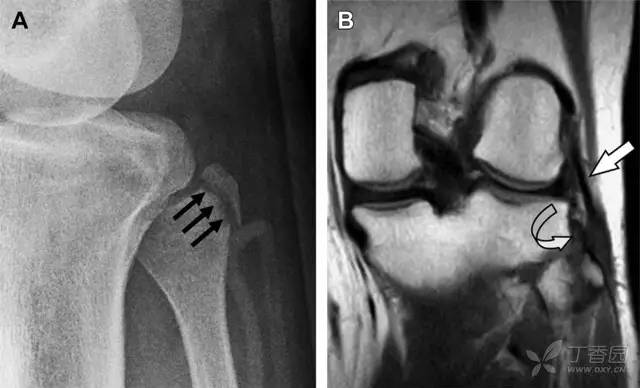

23 单纯肱骨大结节骨折

与其它肱骨近端骨折不同,单纯肱骨大结节骨折常发生于年轻人。肱骨大结节骨折常由撞击或剪切/撕脱损伤所致:

撞击包括直接撞击、肩峰撞击、上关节盂撞击(极度外展时);

剪切/撕脱损伤常发生于肩关节前脱位。

在常规前后位片上,大结节与肱骨头重叠,骨折不易发现,外旋位前后位片有助于诊断。

图 1 大结节骨折。(A)脂肪抑制序列斜冠状位 MRI,显示肱骨大结节线性骨折无移位(箭头)与周围骨水肿;(B)外旋位前后位(AP)片,证实大结节骨折(箭头),典型的骨折愈合过程中的骨吸收表现;(C、D)初诊时内旋位、外旋位前后位片,初诊时漏诊,仔细回顾影像,内旋伞下可见双密度影(椭圆),骨皮质中断(箭头)

24 无移位的桡骨头/颈骨折

多发生于摔倒时,手掌撑地,受到轴向、外翻应力所致。常规的前后位片容易漏诊,常需加拍内斜位、外斜位、桡骨头-肱骨小头位片。后脂肪垫可见(位于鹰嘴窝内,一般不可见)和/或前脂肪垫抬高常提示骨性损伤。

图 2 桡骨头骨折。前后位(A)和侧位(B)片示后脂肪垫抬高(黑色箭头),前脂肪垫抬高(白色箭头),呈「帆船征」,其它表现正常;外斜位(C)和桡骨头–肱骨小头位(D)示桡骨头关节内骨折线(虚线黑箭头)累及桡骨颈(虚线白箭头)

25 肩胛骨骨折

肩胛骨几何形状复杂,受到邻近其它骨性结重叠阻挡,且肩胛骨骨折少见,因此容易漏诊。当存在解剖变异时,诊断更为困难。

图 3 肩胛骨骨折正侧位片:由于骨块的叠加,(A)前后位片示「V」形高密度影(*),肩胛颈下方可见骨皮质碎片(箭头);(B)侧位片示骨皮质中断,骨折段移位,但由于肱骨的重叠遮挡,决断往往比较困难

26 喙突骨折

喙突骨折可发生于直接*力暴**、肩关节脱位过程的肱骨头撞击、以及撕脱骨折(肱二头肌短头、喙肱肌)。

其中喙突基底部骨折最多见,常发生于直接*力暴**或肱骨头前脱位,骨折可延伸至关节盂。

而撕脱骨折多为喙突尖部的骨折。需要加拍腋位和 Stryker 位片(X 射线束以喙突为中心并头倾 10°,手臂外展,这样可以避开骨性结构的阻挡)。

有时,负重位片可发现并存的肩锁关节脱位,将有助于诊断。

图 4 喙突骨折。66 岁男性患者,猎枪射击后右肩前方疼痛。(A)内旋位前后位片投影隐约可见喙突基底部骨折(白色箭头),(B)外旋位前后位片投影结构存在重叠,(C)腋位投影时可良好显示。(D~F)喙突骨折伴 Hill-Sachs 损伤:肩关节脱位后慢性疼痛,喙突骨折块(*)向前外侧移位(双箭头),在外旋前后位(D)及腋位(E)片上均可显示,在内旋位前后位(F)片上,喙突被遮挡,但可见肱骨头 Hill-Sachs 损伤。(G、H)喙突骨折伴肩锁关节脱位,肩锁关节分离(白色双箭头),而喙锁间距正常(黑色的双箭头),应警惕喙突骨折。(I)喙突与肩峰骨化中心:针对未成年人,喙突与肩峰骨化中心可同时存在,易与骨折混淆,此时,拍对侧的 X 线片对比将有助于诊断。